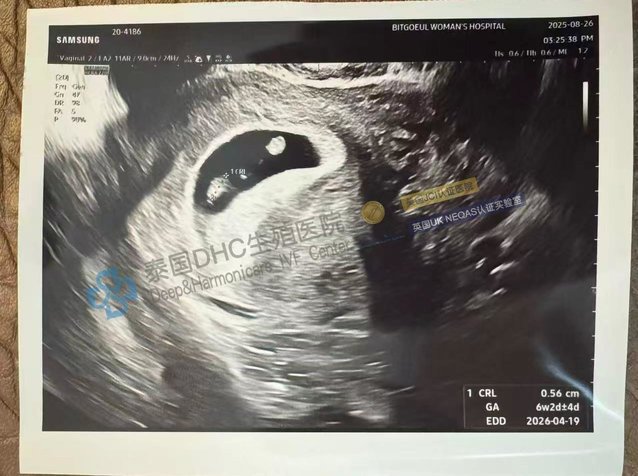

2025-09-08本文將帶您見證泰國(guó)DHC生殖醫(yī)院如何挑戰(zhàn)“不可能”,為高齡客戶創(chuàng)造生命奇跡。我們將聚焦三個(gè)振奮人心的故事:一位40歲勇敢媽媽如何移植“嵌合體胚胎”并成功見到胎心...

2025-09-05本文將帶您完整體驗(yàn)DHC的全周期好孕路徑。我們將聚焦三個(gè)環(huán)環(huán)相扣的真實(shí)故事:一位33歲印尼客戶如何克服子宮瘢痕、甲狀腺異常、精子高碎片率“三重難題”,喜獲4枚健...

2025-09-03本文將帶您見證泰國(guó)DHC生殖醫(yī)院如何將“地獄級(jí)”難度的求子之路,逆襲為圓滿結(jié)局。我們將聚焦兩大“組合拳”案例:一位原發(fā)不孕3年、AMH僅0.5并患有腺肌瘤的客戶...

2025-09-02本文將揭示泰國(guó)DHC生iac生殖醫(yī)院如何成為復(fù)雜不孕癥的“終點(diǎn)站”。我們將聚焦三個(gè)“硬核”案例:如何為患有甲亢、免疫等多重難題,且在廣醫(yī)三院0養(yǎng)囊的客戶成功驗(yàn)孕...

2025-09-01本文將帶您見證泰國(guó)DHC生殖醫(yī)院如何將“挑戰(zhàn)”變?yōu)椤捌孥E”。我們將聚焦三個(gè)由頂級(jí)專家主導(dǎo)的成功案例:一位34歲、AMH僅0.7的客戶如何獲1男1女健康胚胎;一位...

2025-08-28本文將深入剖析泰國(guó)DHC生殖醫(yī)院如何為經(jīng)歷復(fù)發(fā)性流產(chǎn)及多重婦科疾病的客戶,實(shí)現(xiàn)從“苦盡甘來”到“聽見花開”的全過程。我們將聚焦一個(gè)終極挑戰(zhàn)案例的成功,并分享查雅...